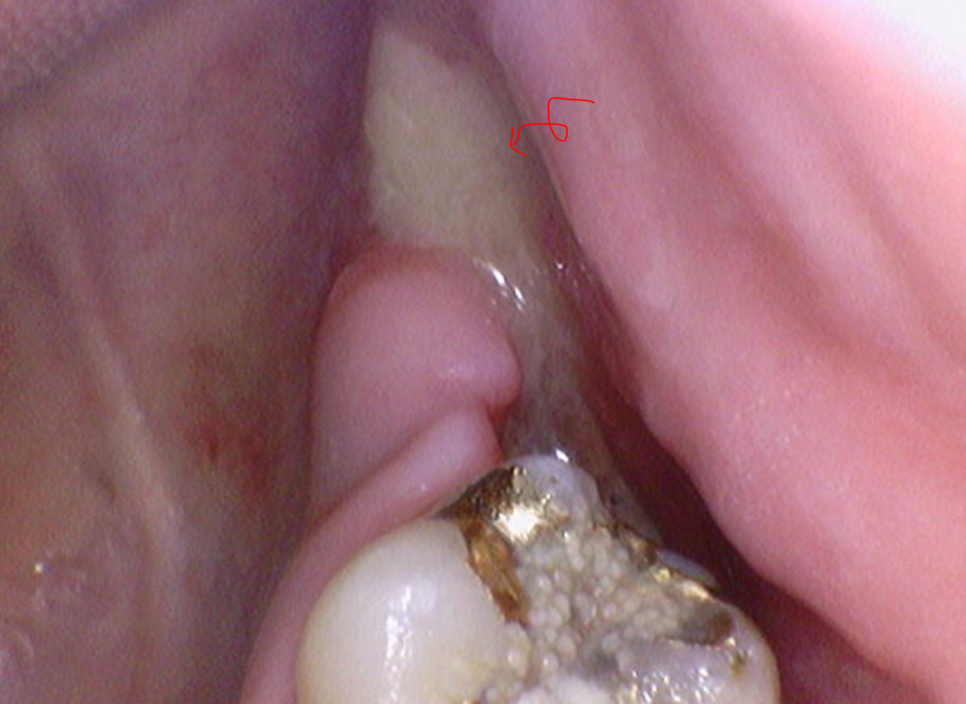

심한 경우는 노란색 농이 나오기도 하고요~

241224 심한경우 노란 농이 나와요!!!